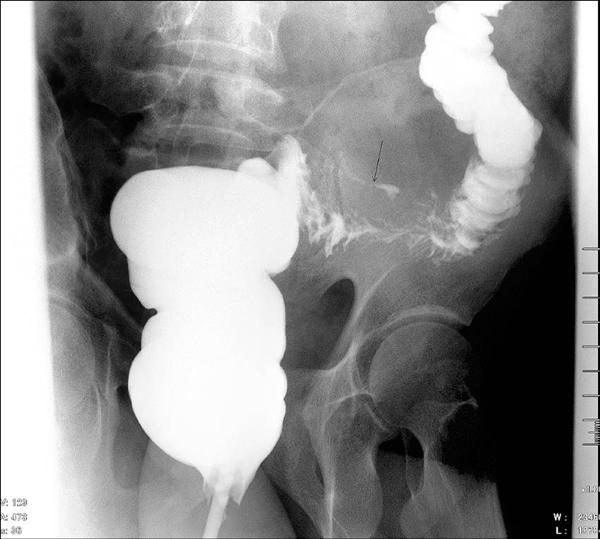

專業醫師提醒民眾,如果發現持續性的泡沫尿、下肢浮腫、排尿疼痛,尿液顏色異常呈現血尿或濃茶色等情況,應立即就醫檢查,透過專業的尿液檢測和腎功能評估,才能及早發現潛在的健康威脅!

看似微不足道的泡泡尿,實則可能是身體發出的警訊,千萬不可掉以輕心!